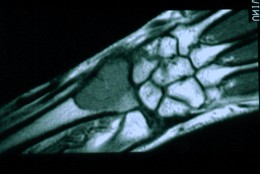

Il tumore bruno è una lesione dell'osso che può insorgere quando l'attività degli osteoclasti aumenta eccessivamente, come ad esempio in corso di iperparatiroidismo A dispetto del nome, non si tratta di un vero tumore, anche se può essere scambiato per tale I tumori bruni hanno aspetto radiotrasparente ai raggi x. Bruno had an oncology checkup and unfortunately they found a lump on his left temple It was aspirated and confirmed to be a mast cell tumor When a tumor is aspirated it means they put a needle into the lump and pull out cells to be tested The fluid that was extracted has been sent away for more testing. This page was last edited on 25 February 19, at 1549 Files are available under licenses specified on their description page All structured data from the file and property namespaces is available under the Creative Commons CC0 License;.

During the 62nd American Society of Hematology (ASH) Annual Meeting and Exposition, the Multiple Myeloma Hub spoke to Bruno Paiva, University of Navarra, Pamplona, ES We asked, Can circulating tumor cell assessment by flow replace bone marrow aspirates to monitor smoldering multiple myeloma (SMM)?. Il tumore bruno è una lesione dell'osso che può insorgere quando l'attività degli osteoclasti aumenta eccessivamente, come ad esempio in corso di iperparatiroidismo A dispetto del nome, non si tratta di un vero tumore, anche se può essere scambiato per tale I tumori bruni hanno aspetto radiotrasparente ai raggi x. Additional terms may apply.